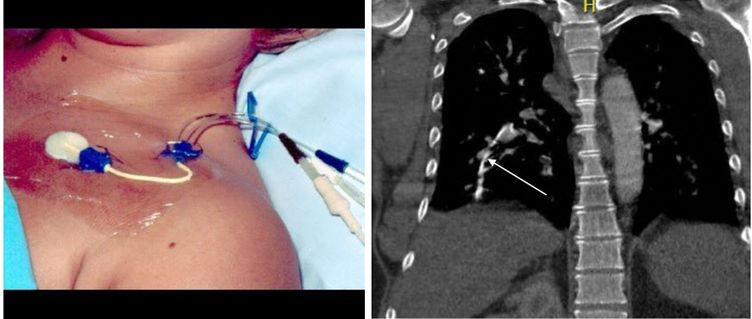

Central venous catheter (CVC) is an indwelling device placed either in internal jugular vein, femoral vein, or subclavian vein. CVC are employed for administration of fluids and medications. Blood can also be drawn from central line to run laboratory investigations. Central vein catheters are superior to peripheral IV lines with respect to large amount of fluid and medication administration. It can be left in body for longer time periods as compared to peripheral lines. Typical immediate complications of placing a central venous catheter are injury to structures adjacent to the catheter, hemorrhage, hemothorax, arrhythmias, and phlebitis. Infection and thrombosis could arise as long-term complications. A journal reported a case of 46 years old gentleman, who presented to ER in with picture of septic shock. Patient was a known alcoholic, a type II diabetic, and had a liver injury from prior laparotomy. Patient also had history of ICU admission 28 years back. On examination, patient was febrile, tachycardiac and hypotensive with deteriorating oxygen saturation. Patient was not responsive to fluid resuscitation hence epinephrine was administered. Broad-spectrum antibiotics were initiated. Laboratory investigations revealed severe metabolic acidosis and acute kidney injury and subsequent anuria. Inflammatory markers were also raised. Total body CT scan was conducted to determine the source of infection. A foreign body was identified in pulmonary arteries . this foreign body was thought to be the remnant of central venous catheter inserted 28 years back. Any surgical intervention was not possible due to hemodynamic instability. The patient, despite of aggressive resuscitation and treatment, could not survive and died within 18 hours of admission. Autopsy revealed presence of foreign body in pulmonary arteries, attached with arterial wall by multiple adhesions. This foreign was the remnant of the catheter that was placed 28 years back. Numerous bacterial colonies were seen on catheter. Enterococcus faecium was cultured from the remnant of CVC, hence, was the source of sepsis. This case report encouraged proper removal of CVC, and vigilant examination of the CVC to look for any missing parts. Source An Unexpected Case of Late Fatal Central Venous Catheter Sepsis: A Case Report https://www.thieme-connect.com/products/ejournals/html/10.1055/s-0040-1713415 Image on right side shows presence of remnant of CVC taken from https://www.thieme-connect.com/products/ejournals/html/10.1055/s-0040-1713415 https://www.youtube.com/watch?v=ubwWEXji79U